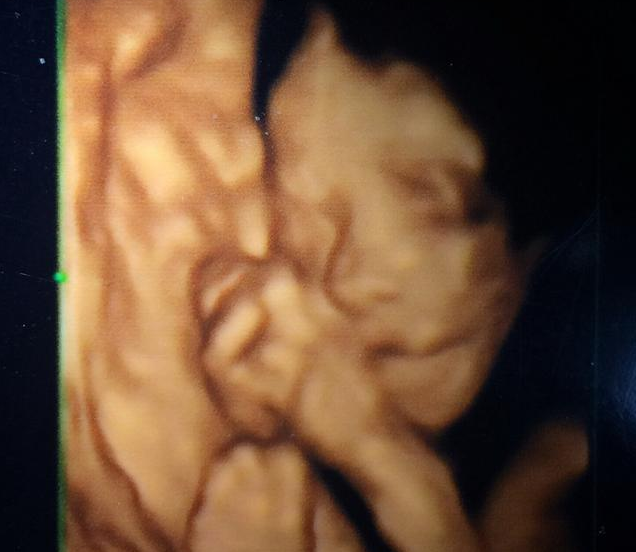

在做四維彩超時,很多時候并不如孕媽們想得那么容易,胎兒總是會趴著,導致無法篩查胎兒面部異常情況,很容易導致四維檢查失敗,那么,做四維彩超時寶寶不配合怎么辦呢?接下來八寶網小編就來說一說。

四維彩超胎兒總是趴著怎么回事

做四維彩超的時候無數孕媽并非是順利的,因為很多胎兒總是趴著。

首先一方面是因為胎寶寶在媽媽的子宮內喜歡腹部朝內,背部朝外的蜷曲姿勢。這種姿勢是自然的自我保護姿勢,既有安全感,還有利于寶寶的神經系統發育。

其次是因為在做四維彩超時,胎兒大多會有一種生疏的感覺,這是因為胎兒的感知能力特別強。